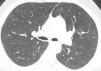

Centrilobular ground-glass nodules were found to be more prominent in the upper lobes of the lungs in thorax computed tomography (CT) (Fig. 1a). Abdominal CT and ultrasonography were found to be normal. Endoscopic biopsy for stomach pain was reported as eosinophilic gastritis. Eosinophilic infiltration was observed on transbronchial lung biopsy. Numerous eosinophilic granulocytes (40%) were observed in bone marrow biopsy without increased blast cells. A prominent mast cell population was not observed. There was no malignant infiltration. FIPLI-PDGFRα mutation, JAK-2 mutation and Philadelphia chromosome were also found to be negative.

In our case, differential diagnosis was performed for primary (hematopoietic neoplasms with HE) and secondary HES, (helminth infections, allergic reactions, atopic diseases, drug reactions (allergic or toxic), Hodgkin disease, B- or T-cell lymphoma/leukemia, Langerhans cell histiocytosis, indolent systemic mastocytosis, solid tumors/malignancy, allergic bronchopulmonary aspergillosis, chronic inflammatory disorders, autoimmune diseases and lymphoid variant of HES), organ-restricted conditions accompanied by HE (eosinophilic gastrointestinal disorders, eosinophilic pneumonia, dermatologic diseases, etc.) and specific syndromes accompanied by HE (Gleich syndrome, Churg-Strauss syndrome, eosinophilia myalgia syndrome, Hyper-IgE syndrome).1–6 The patient was diagnosed with idiopatic HES after exclusion of all primary and secondary causes and exclusion of other conditions and syndromes. The patient was started on imatinib mesylate therapy with 400mg/day because he did not respond to corticosteroids (CS) and hydroxyurea therapy. The treatment was reduced to a 100mg in the third month of treatment due to normalization of eosinophil levels and disappearance of all complaints. The ground-glass nodules disappeared after 1 year of imatinib treatment (Fig. 1b).